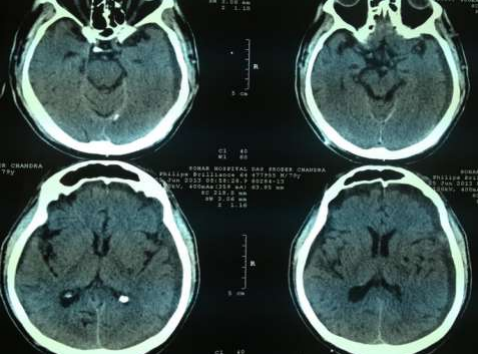

Radiology

Fig 1,2,3,4,5,6,7,8,9,10,11,12,13,14,15

Figure 2

Figure 3